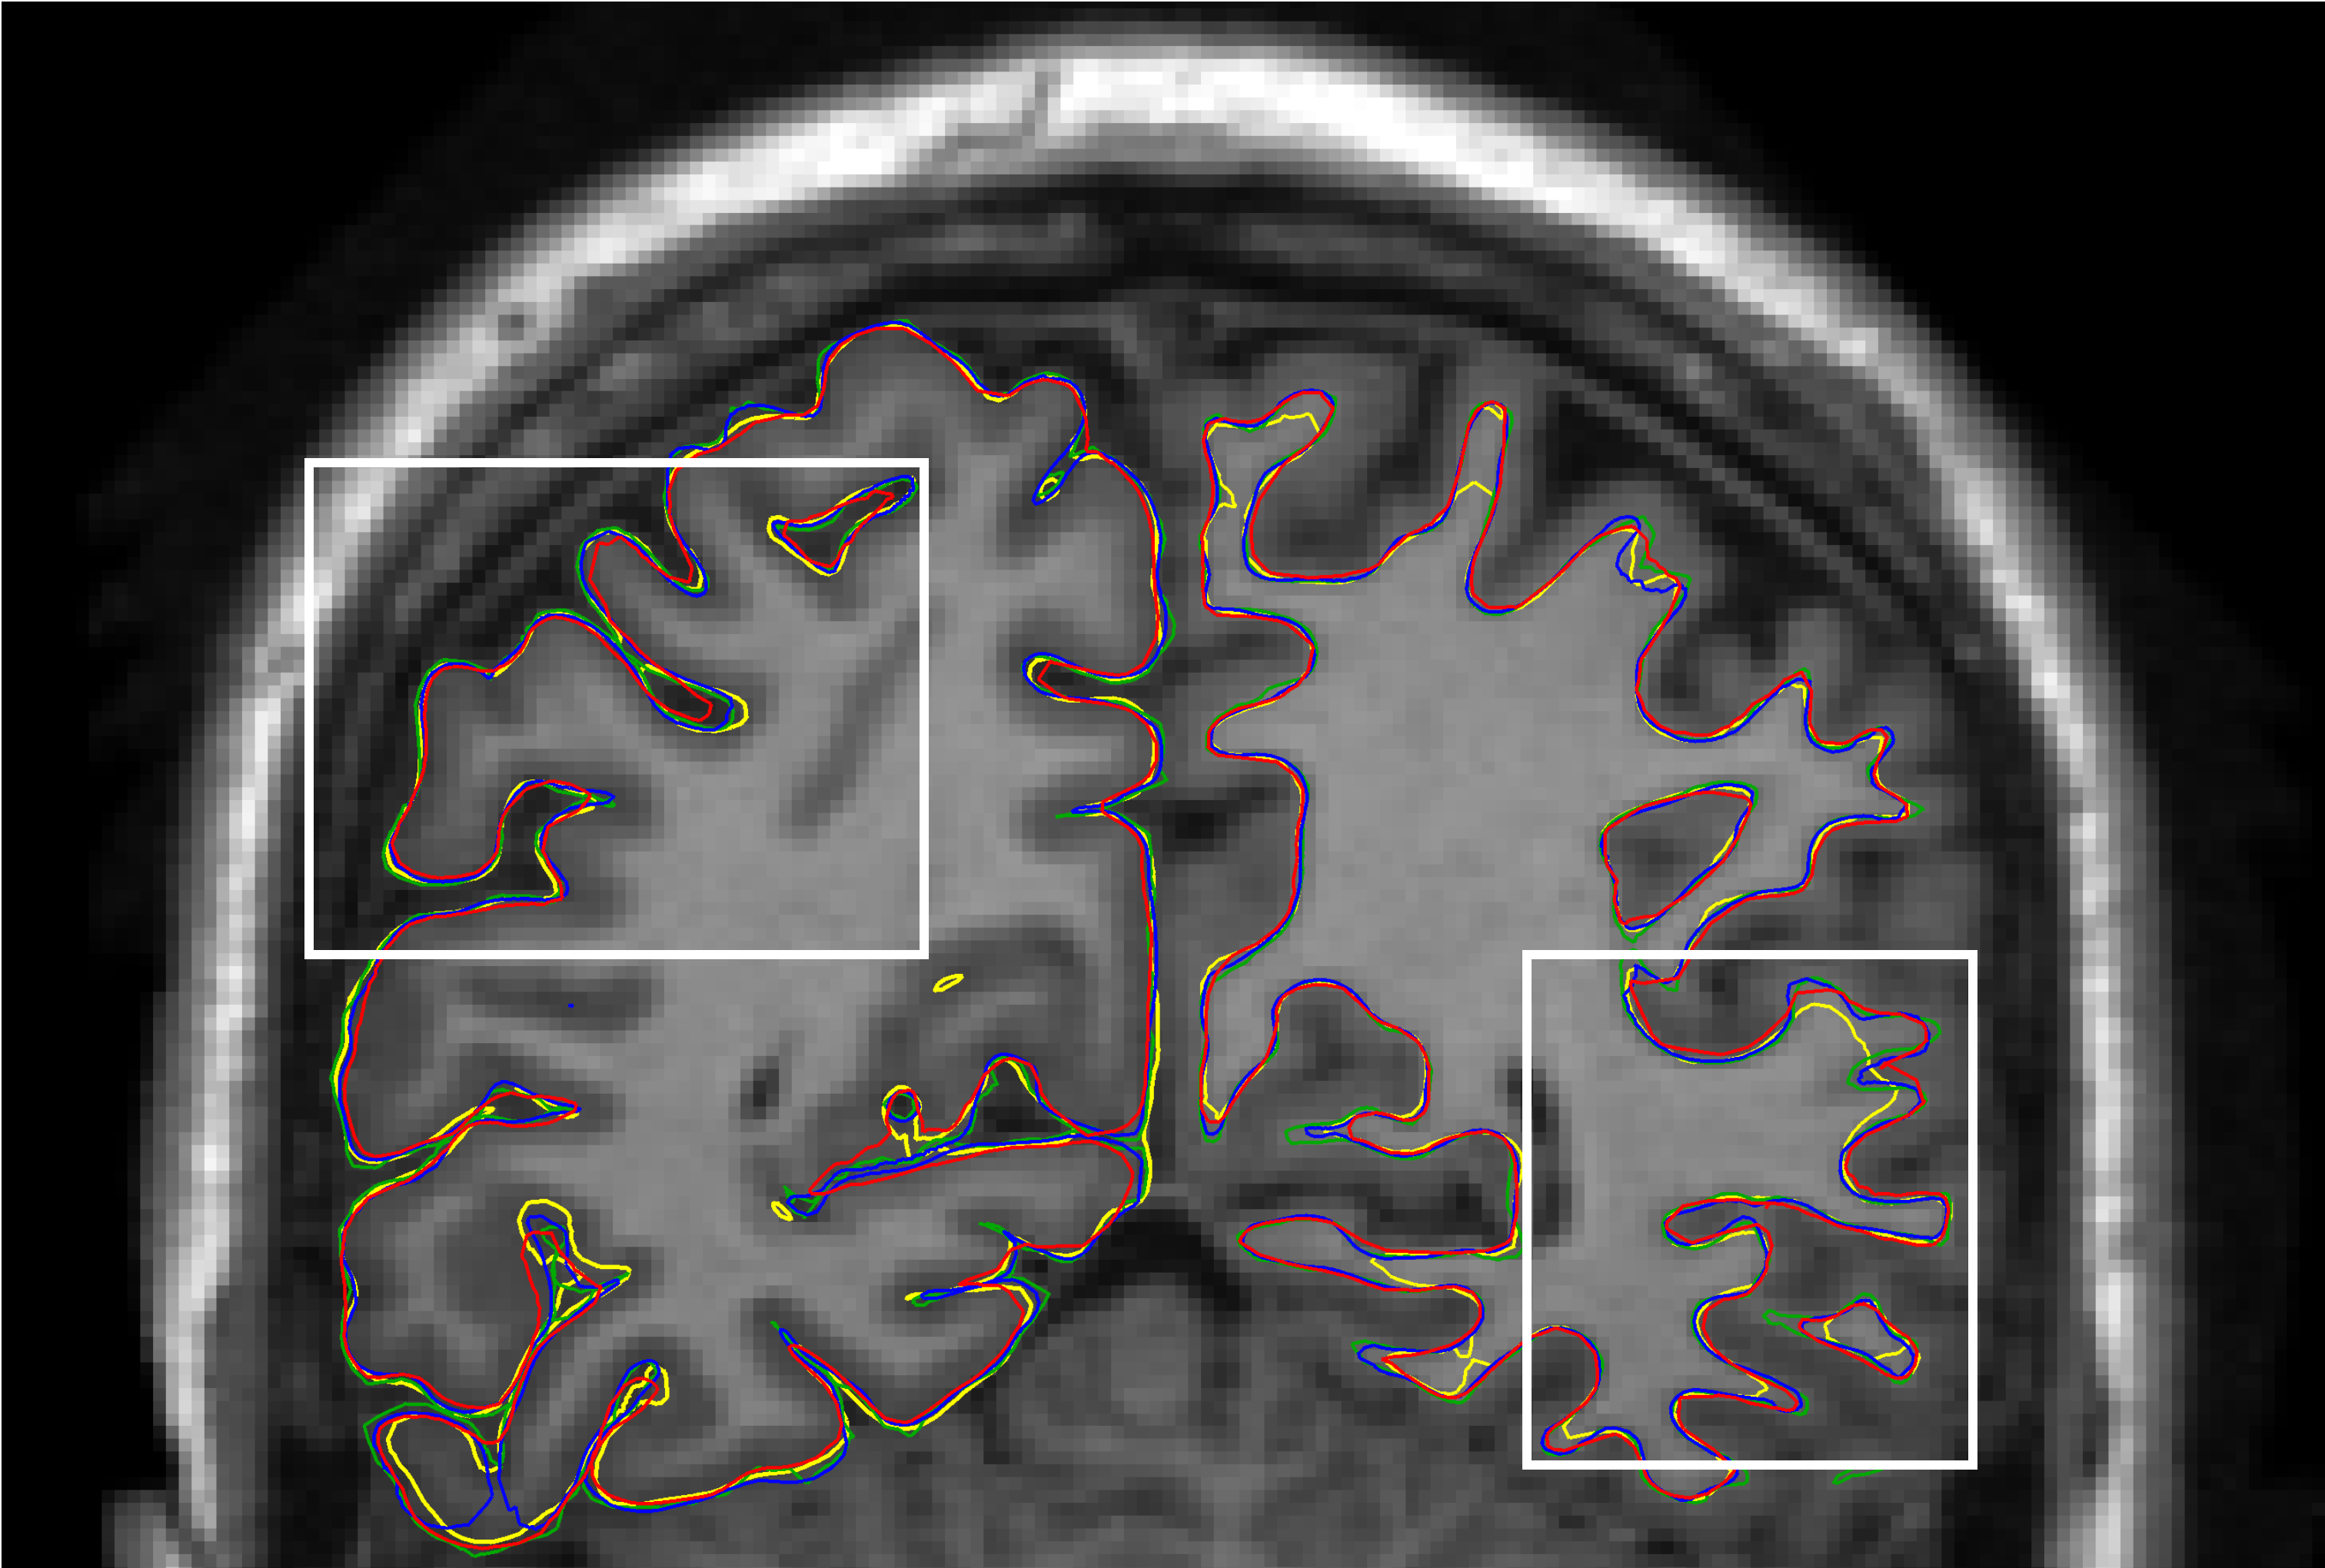

Figure 5: Cortical surface reconstructions: SimCortex (yellow), CFPP (blue), V2C (red), and ground truth (green). (a) Coronal view with MRI overlay. (b) RH pial surfaces detail. (c) LH white matter surfaces detail.

3.3.3 Visual Analysis

Figure 5 compares cortical surface reconstructions by SimCortex, CFPP, and V2C against ground truth surfaces. SimCortex captures deeper sulci in some regions but occasionally produces smoother surfaces lacking detailed curvature; CFPP is generally accurate; V2C is less precise. For the white matter surfaces, CFPP and V2C closely match ground truth sulcal depth, whereas SimCortex shows shallower sulci, indicating a model limitation. Fig. 6 compares SimCortex and CFPP regarding hemispheric intersections. SimCortex (yellow) effectively avoids intersections, while CFPP shows collisions between right (dark blue) and left (light blue) hemispheres. V2C demonstrates hemispheric intersections similar to CFPP.